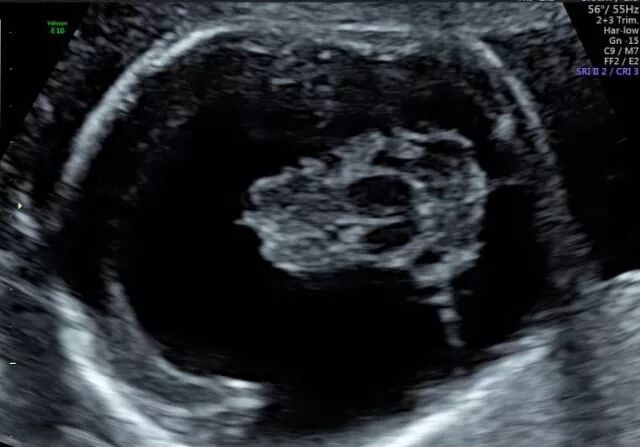

胎儿常见畸形检查图

(柠檬头)